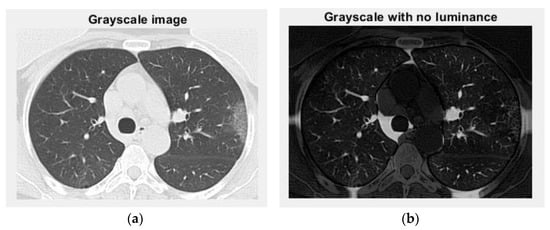

Figure 20 and Figure 21 are the grayscale images with and without luminance of the non-COVID-19 lung CT image, respectively, the filtered versions of the non-COVID-19 lung CT image.

Figure 20. Grayscale versions of the non-COVID-19 lung image: (a) grayscale image and (b) grayscale with no luminance.